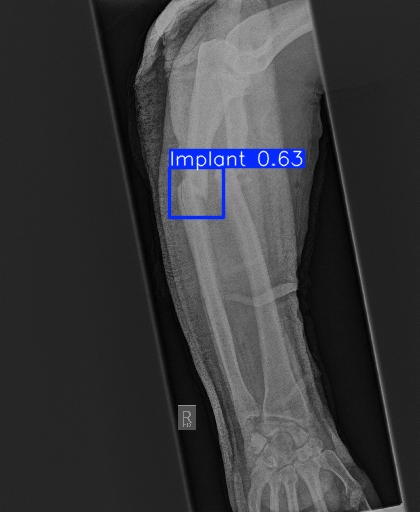

Bone 이미지 데이터 350장 중 Fracture 이미지 50장, Implant 이미지 50장, Bone 이미지 50장을 선별했다.

train과 val은 라벨링을 해야한다. 어제 라벨링을 했었지만, Fracture는 좀 넓게 잡고, Implant는 최대한 여러개로 쪼개는 느낌으로 라벨링을 다시했다.

class 이름을 반대로 해뒀다...

| conf | 0.3 | 원래 0.9였는데 어제 결과가 너무 안 나와서 0.5로 바꿨다가 다시 0.3으로 바꿨다 |